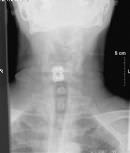

Les Posted September 18, 2010 Report Posted September 18, 2010 caused by decades of affirmative nodding. Click to Enlarge 25.82 KB

Tom Raymond Posted September 18, 2010 Report Posted September 18, 2010 caused by decades of affirmative nodding. Click to Enlarge 25.82 KB Ouch! So just how long have you been married?[:-angel]

gtblum Posted September 18, 2010 Report Posted September 18, 2010 What the hell is that thing? Is it one of those chips they use for finding lost people?